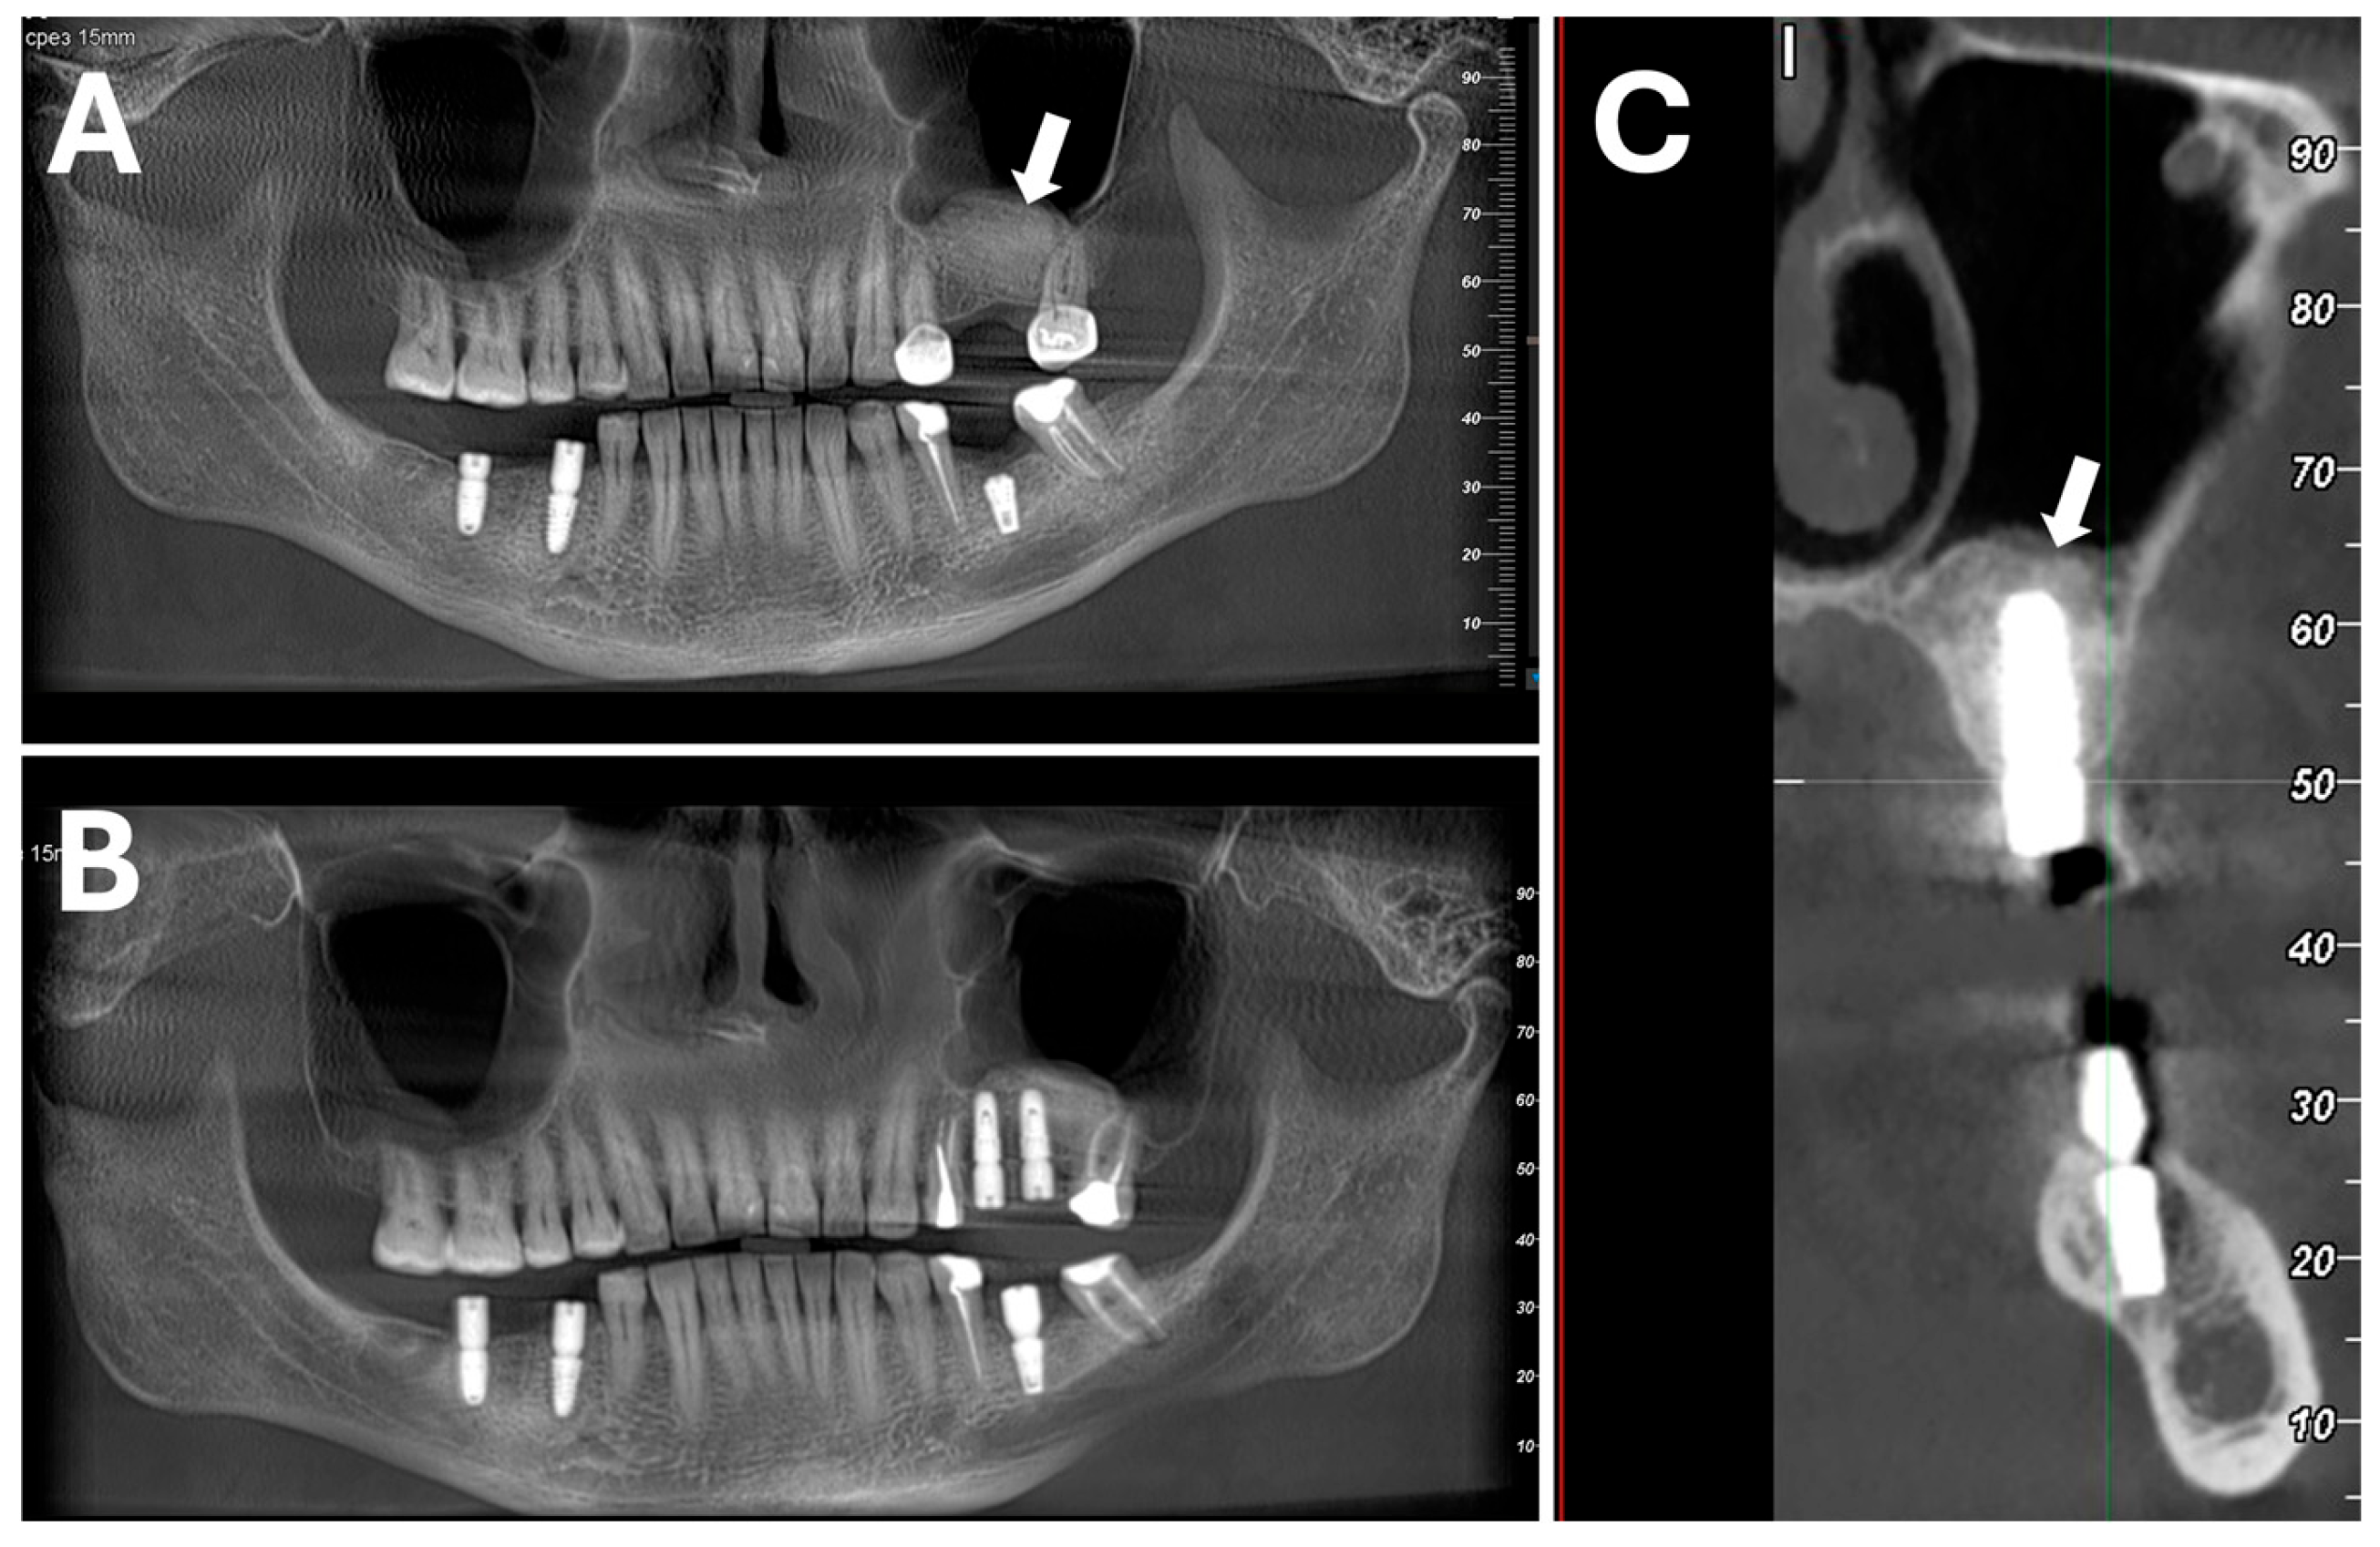

- Sapoznikov, L.; Haim, D.; Zavan, B.; Scortecci, G.; Humphrey, M.F. A novel porcine dentin-derived bone graft material provides effective site stability for implant placement after tooth extraction: A randomized controlled clinical trial. Clin. Oral Investig. 2023, 27, 2899–2911. [Google Scholar] [CrossRef]

| Implant properties | Clinical bone growth | Superior new bone formation, bone-graft integration, and higher radiodensity than a porcine bone graft material with retained ECM at 4 months after mandibular premolar or molar tooth extraction in patients |